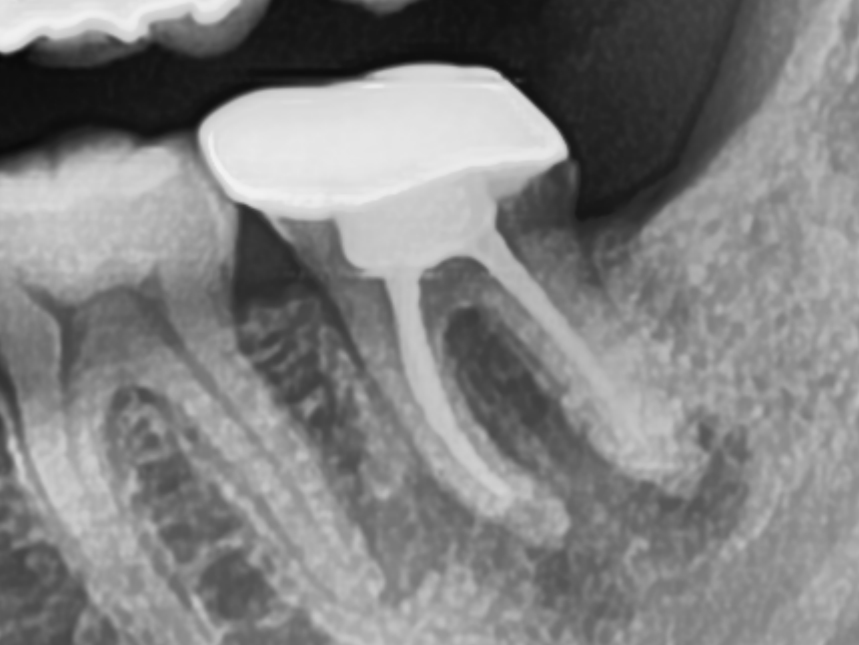

CASE.02 재신경치료

• 재신경치료

기존 신경치료 부분에 염증이 발생하여 재신경치료를 통해 치료

치료전 2023.01.26 / 치료후 2023.02.27